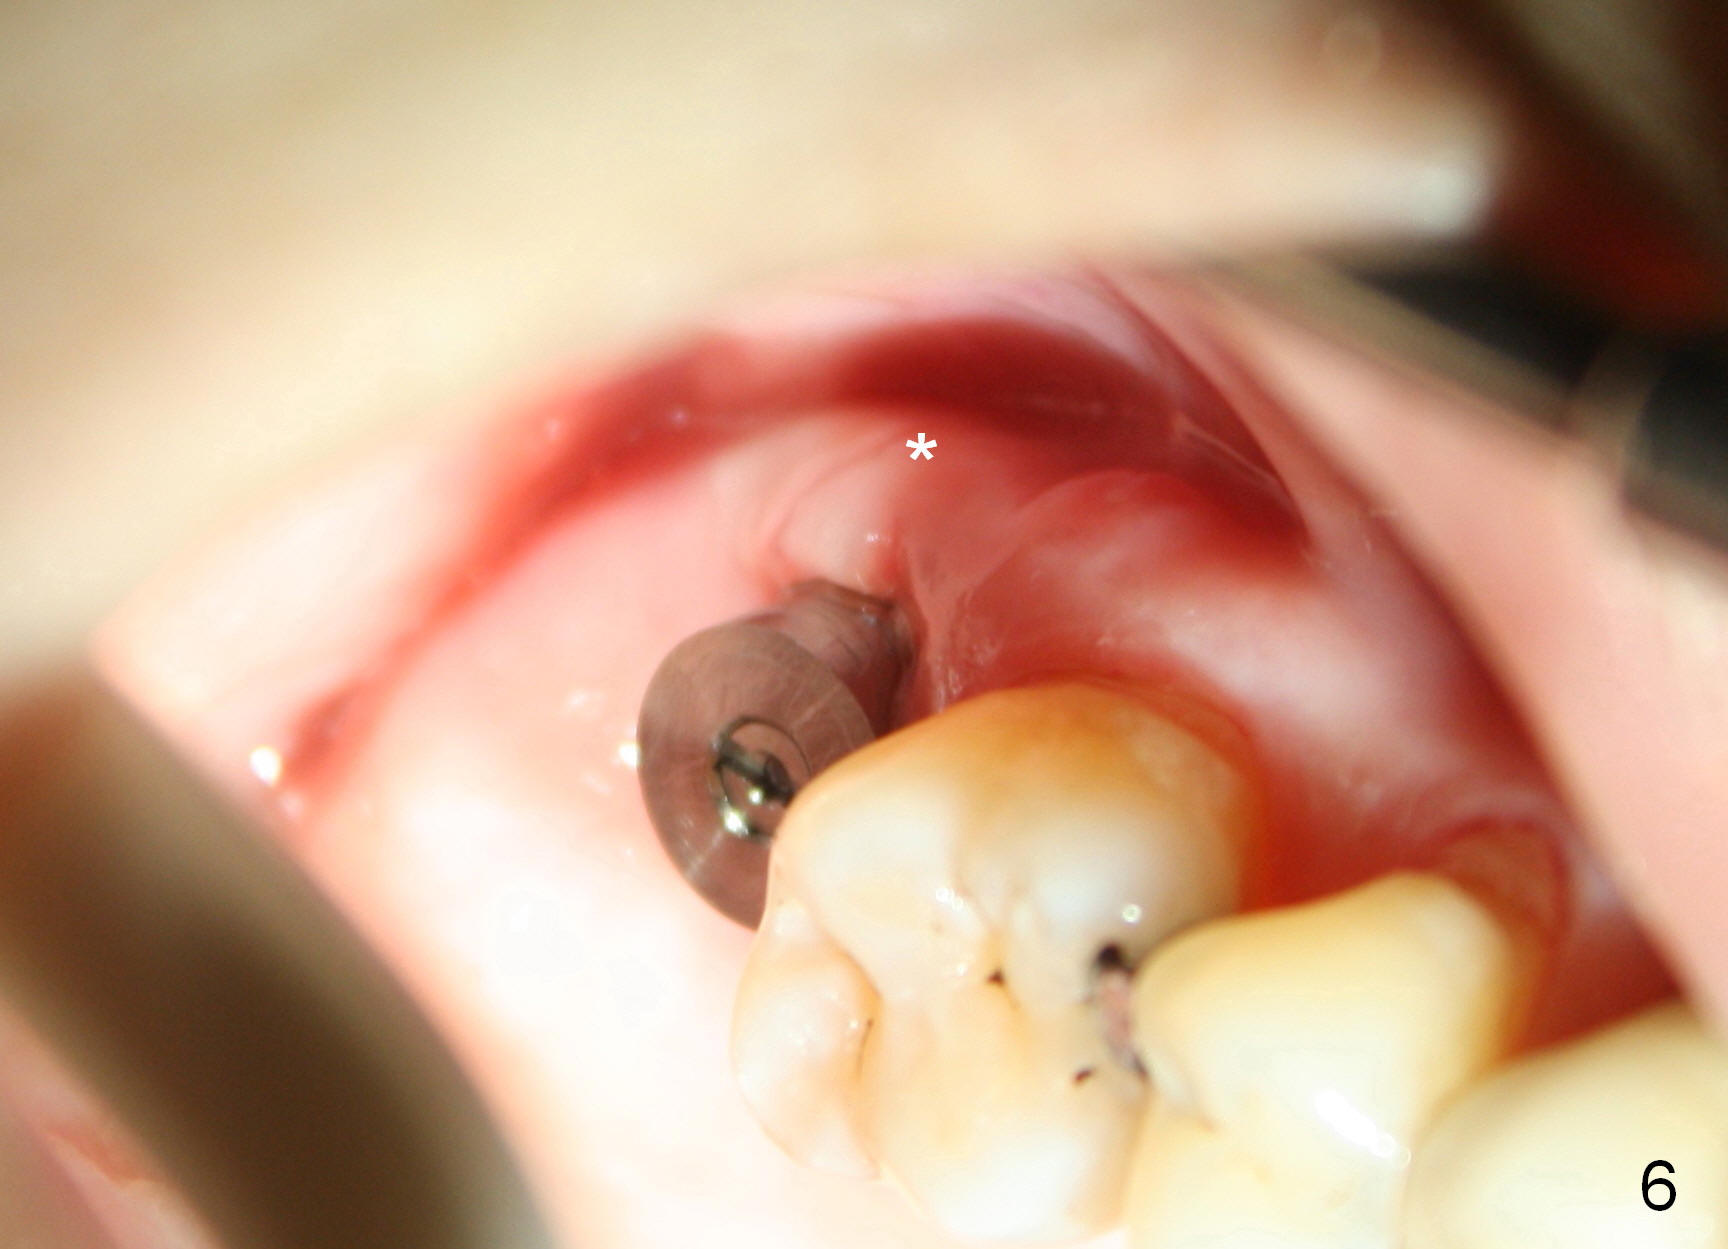

One week later, the lingual portion of the perio dressing is lost (Fig.5 L) while that around the abutment (Fig.4,5 *) and buccal portion (Fig.4 B)are in place. It appears that the abutment stabilizes the perio dressing. The latter helps wound heal. The remaining dressing is left undisturbed for any presumptive further protection. The dressing is off 9 days postop; the gingiva overlying the buccal plate at the site of #2 (Fig.6 *) is slightly lingual to that of the tooth #3.